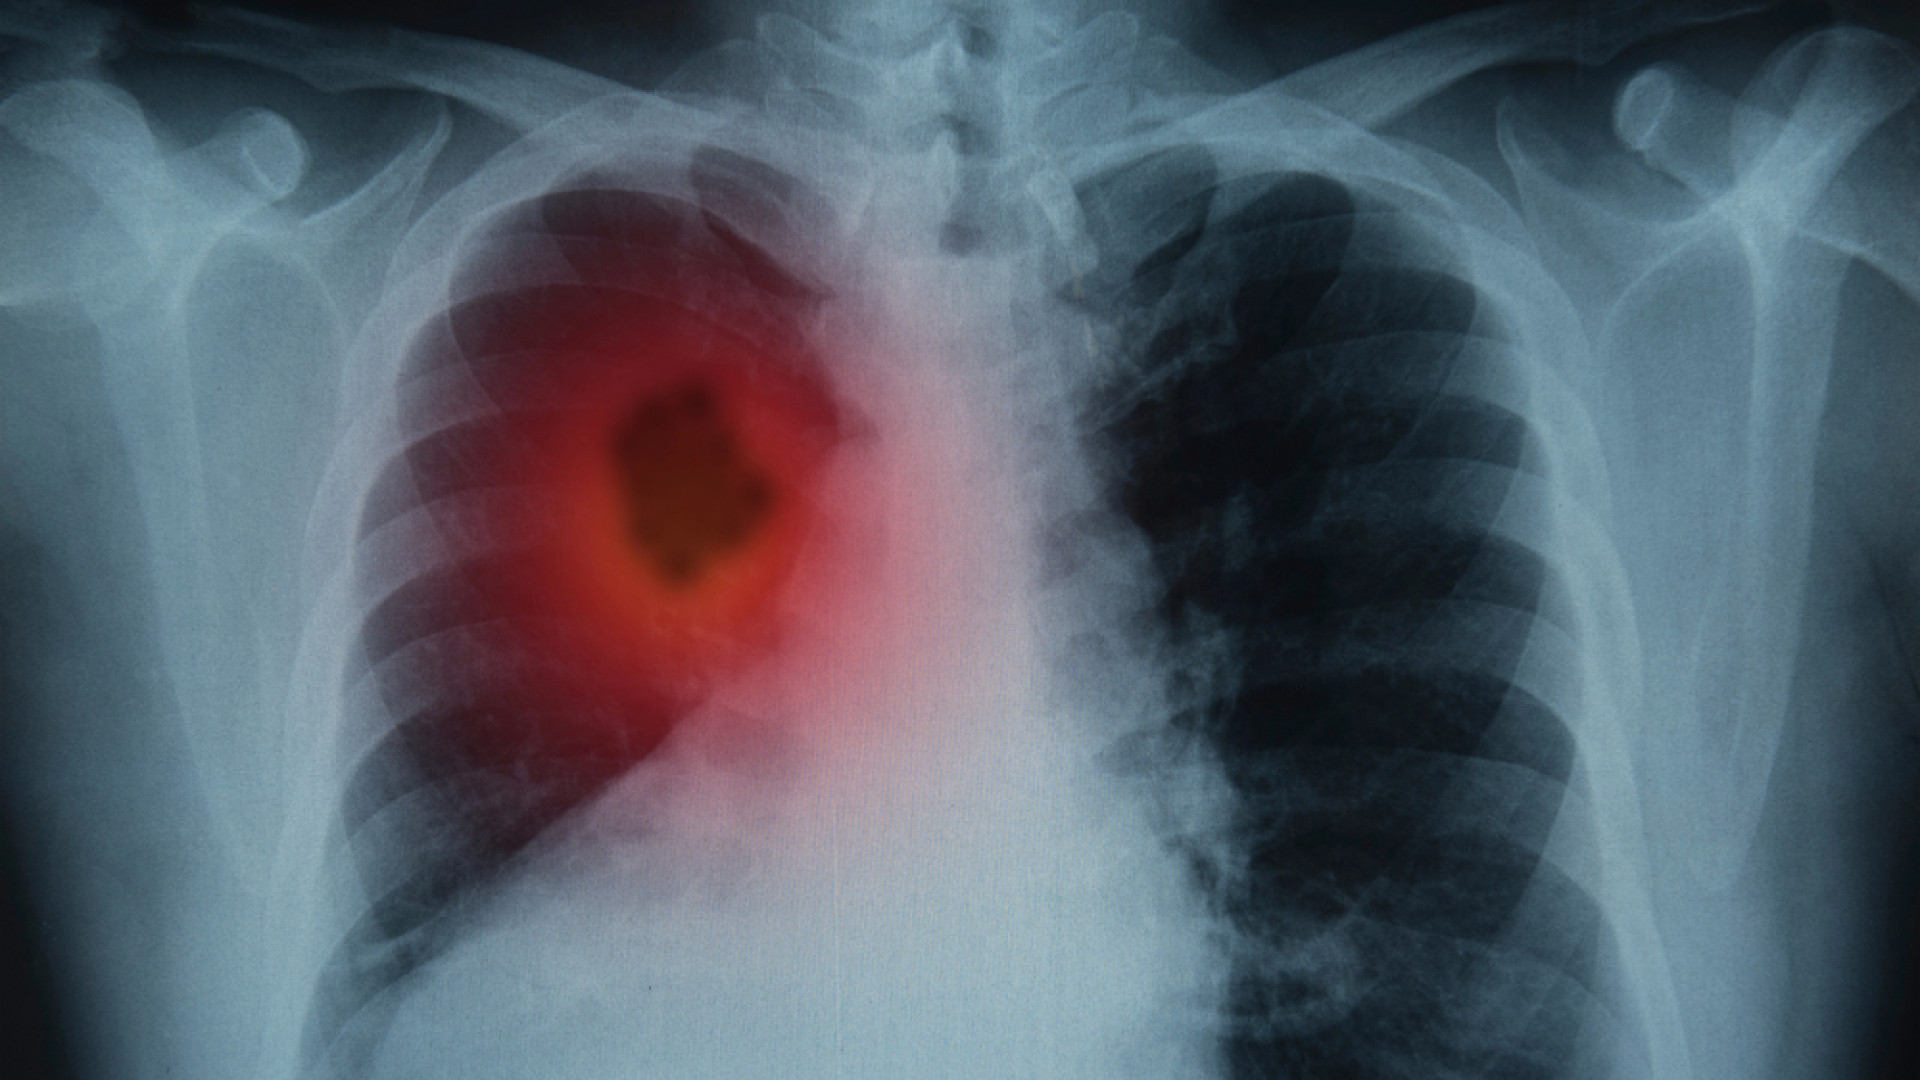

Рак легкого является одним из наиболее агрессивных онкологических заболеваний, но для его диагностики существует действенный метод - НДКТ-скрининг, способный спасти миллионы жизней. Об этом в интервью "Ленте.ру" рассказал заслуженный врач, профессор Петр Яблонский, передает TengriHealth.

Специалист пояснил, что сложность выявления онкологических заболеваний легких обусловлена отсутствием нервных окончаний в нижних отделах дыхательной системы. Поэтому заболевание может долгое время протекать бессимптомно, а отдельные проявления - кашель или усталость - ничего не подозревающие больные часто списывают на простуду или возрастные изменения.

"Без лечения медиана выживаемости у больных даже на первой стадии составляет всего около 16 месяцев. А у нас, согласно официальным данным, 43 процента новых случаев выявляется уже на четвертой стадии", - заявил главный торакальный хирург Минздрава России.

В этой связи, отмечает профессор, врачебное сообщество выступает за внедрение скрининга с помощью низкодозной компьютерной томографии (КТ). Если диагностировать рак легкого на первой стадии, пятилетняя выживаемость пациентов составляет от 92 до 98 процентов, указывает врач.

Профессор напоминает, что положительный эффект от скрининга был установлен специалистами еще в 1990-х годах. В частности, проведенное тогда исследование показало снижение смертности от рака легкого на 25 процентов среди курильщиков старше 50 лет за счет раннего выявления.

Более позднее исследование выявило еще большую эффективность указанного метода - снижение смертности вдвое, подчеркивает специалист.